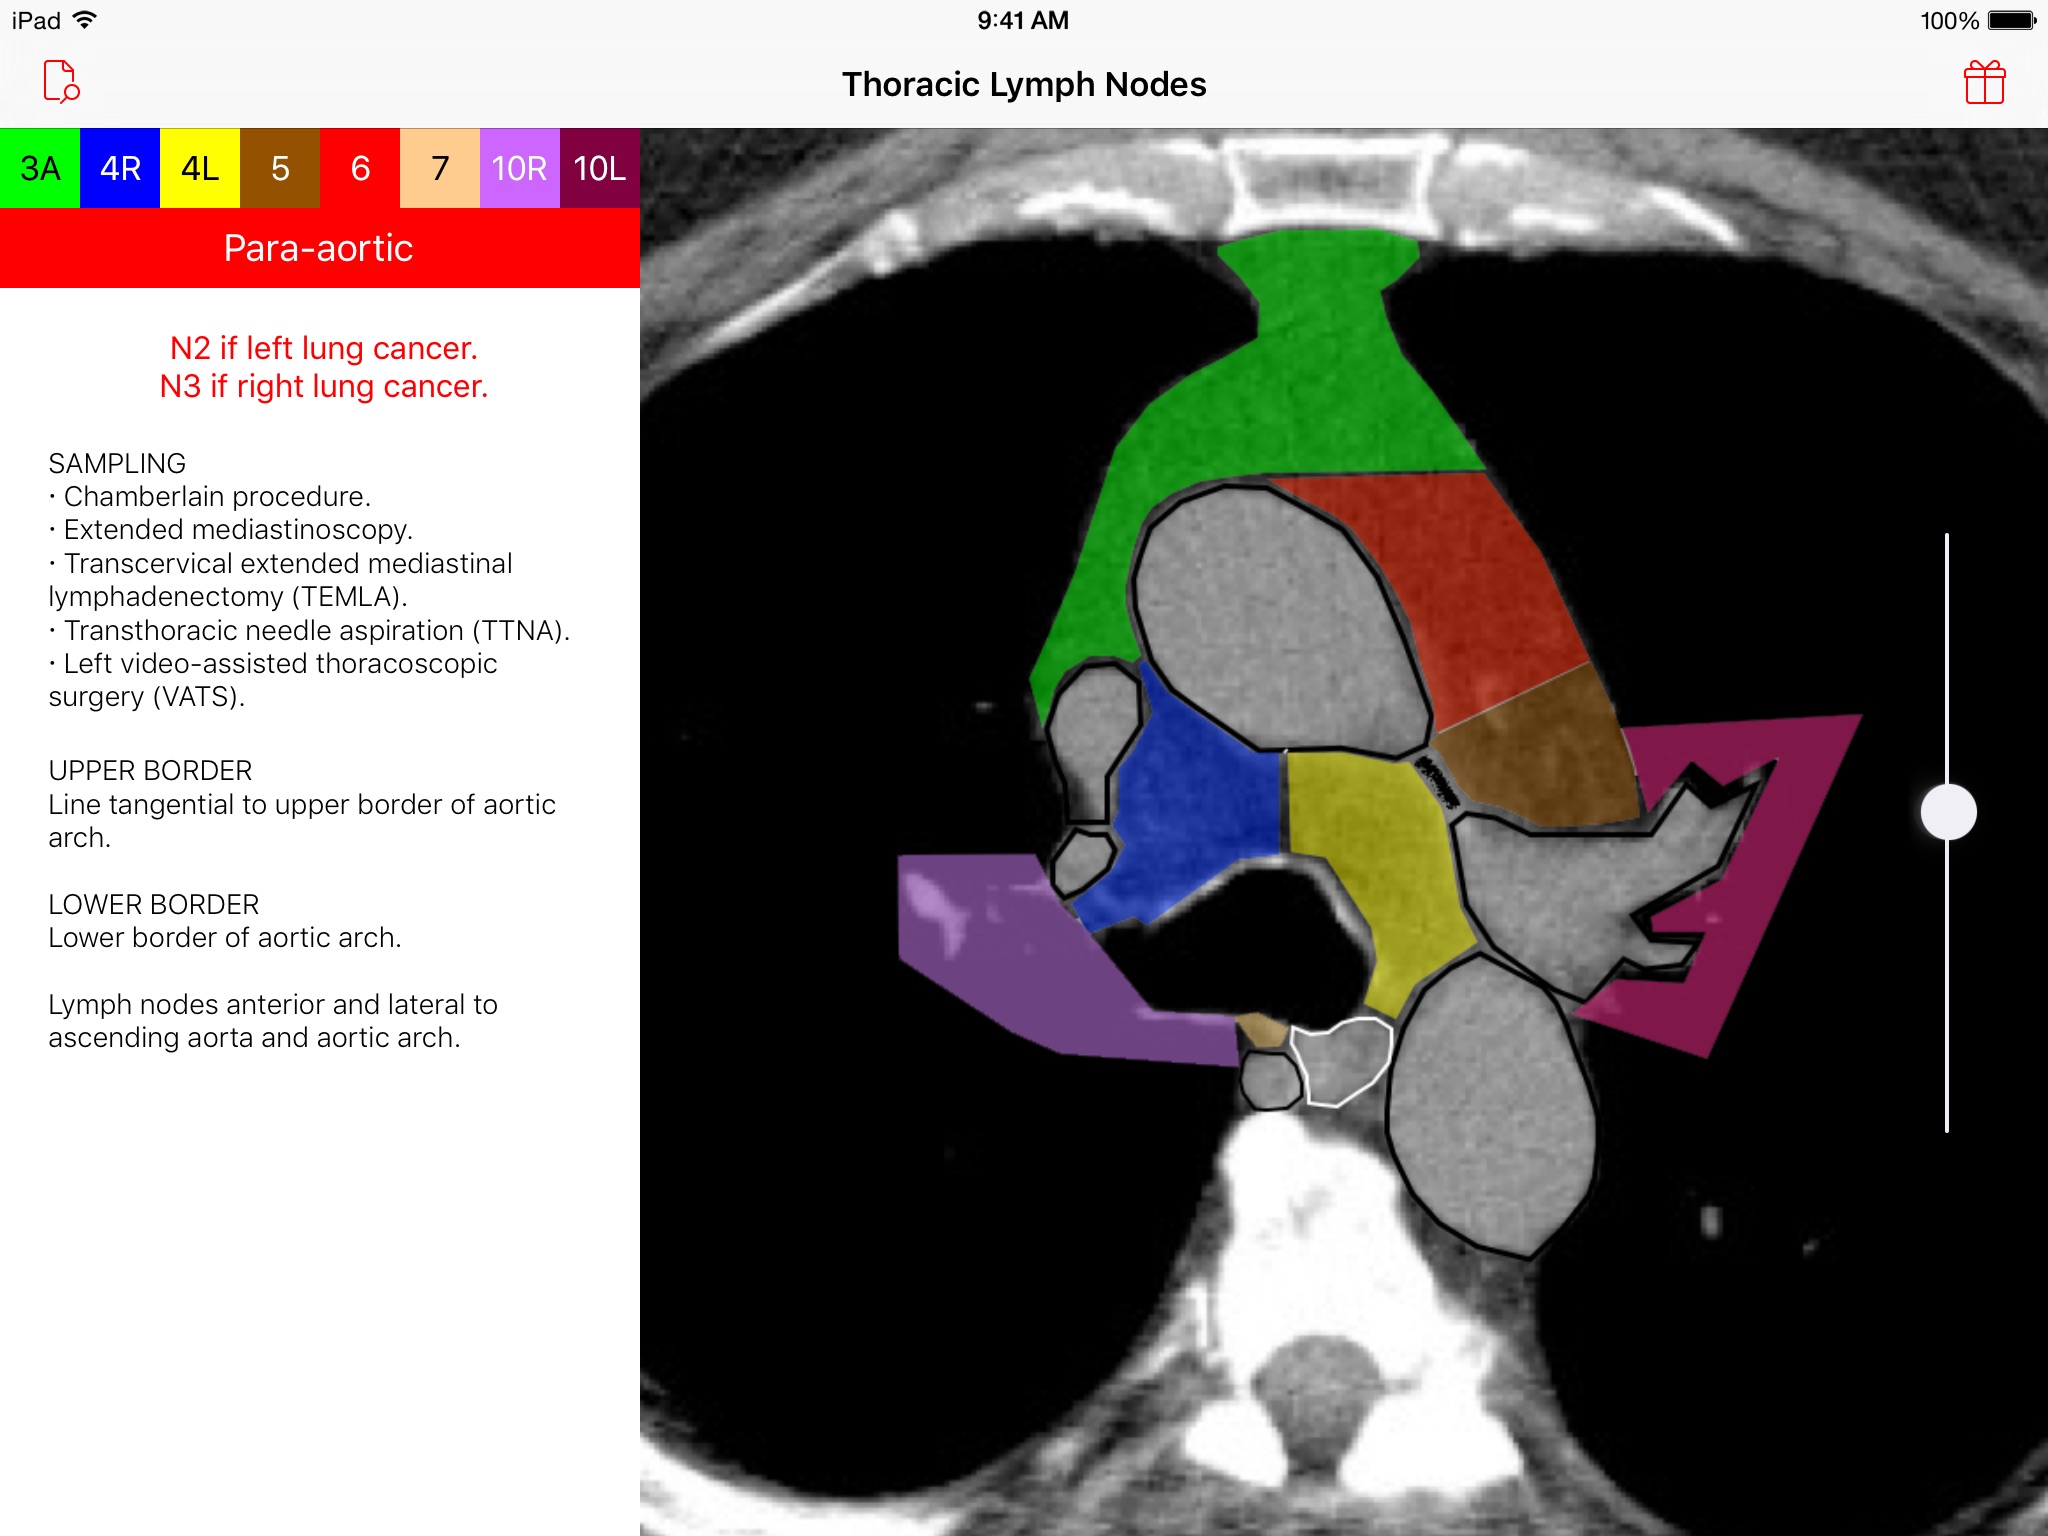

Introducing the Thoracic Lymph Node Map app, an elegant tool that provides healthcare professionals with a color-coded CT lymph node map adapted from the International Association for the Study of Lung Cancer (IASLC) lung cancer project. Effortlessly navigate through CT images of the chest and view beautifully illustrated, color-coded thoracic CT lymph node map anatomic definitions for each lymph node station. Delve deeper and learn more about classification, sampling options, and anatomic details of each lymph node station. Browse · Regional thoracic lymph node station territories · Relationships between different regional lymph node stations within the chest Discover · Clinical regional lymph node classification for each lymph node station · Sampling options for each lymph node station · Anatomic boundaries for each lymph node station Requirements · A device with iOS 8 or later This app was developed as a service to the medical community and is provided free of charge and free of advertising.